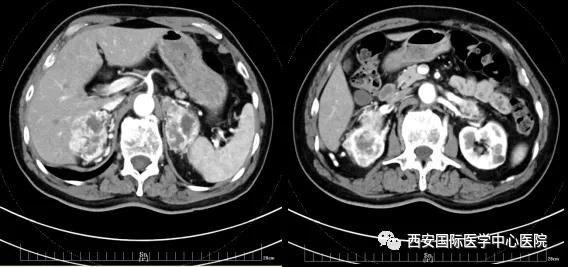

今年七十五歲的患者,來自陜西省商洛市,四月前因腰背部疼痛就診于當(dāng)?shù)蒯t(yī)院,行CT檢查發(fā)現(xiàn)“右腎、雙側(cè)腎上腺占位,前縱膈淋巴結(jié)腫大,雙肺多發(fā)結(jié)節(jié)、胸椎骨質(zhì)破壞,考慮轉(zhuǎn)移瘤”。為進(jìn)一步診斷治療,患者的兒子帶他來到西安某三甲醫(yī)院,查泌尿系CT提示“右腎占位性病變,多考慮腎癌,雙側(cè)腎上腺多發(fā)轉(zhuǎn)移灶,腹膜后多發(fā)腫大淋巴結(jié)”;行穿刺活檢提示“腎透明細(xì)胞癌”;并給予患者口服靶向藥物的治療方案。

自四月份至今,患者一直口服靶向藥物治療(阿昔替尼5mg 2次/日),期間無不良反應(yīng),目前腰背部疼痛癥狀也有所緩解,復(fù)查影像學(xué)資料提示瘤體較前縮小,腫瘤完整切除的可能性明顯提高;而且患者的兒子也是一名外科醫(yī)生,所以他更想為父親完成后續(xù)的手術(shù)治療。

手術(shù)由楊增悅教授主持,舒濤主治醫(yī)師、王東主治醫(yī)師主刀,黃怡醫(yī)師、王平醫(yī)師協(xié)助完成。由于第四代達(dá)芬奇機(jī)器人更加靈活和精準(zhǔn)的特性,手術(shù)全程順利,尤其是完全精準(zhǔn)的“解鎖”了右腎動脈和右腎靜脈的數(shù)十根交互纏繞的分支血管。術(shù)后患者麻醉恢復(fù)后生命體征平穩(wěn),順利返回泌尿外科普通病區(qū)進(jìn)一步康復(fù)。